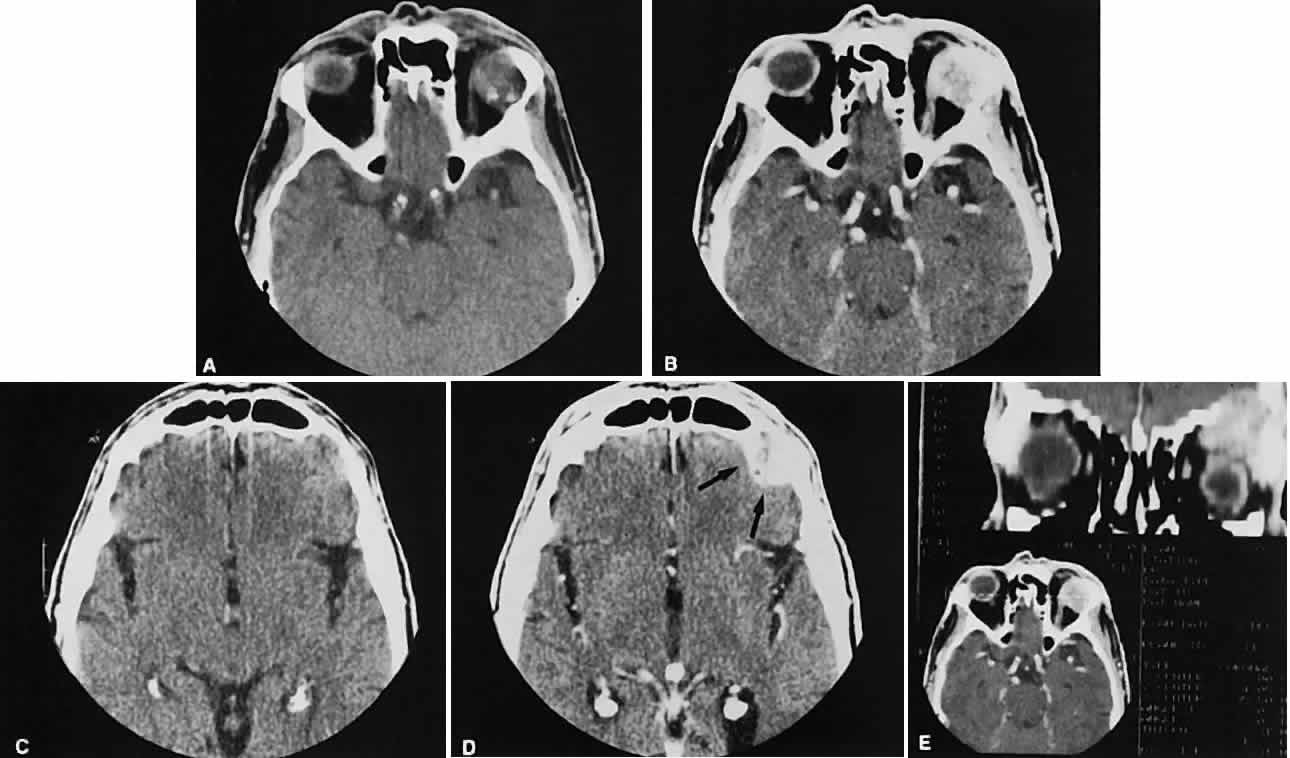

Malignant lesions of the lacrimal gland, conversely, often appear invasive, with bone destruction evident on the CT scan (Fig. 17). Intralesional calcium may be present.63,64 The use of contrast material facilitates detection of lesions that extend beyond the confines of the orbit.

Fig. 17. Adenocarcinoma of the lacrimal gland. A. Unenhanced axial view shows the speckled calcification of a lacrimal gland tumor. B. Contrast-enhanced view at about the same level shows intense enhancement and vascularity. In axial views at a higher level, an unenhanced scan (C) is unremarkable, although a contrast-enhanced view (D) at the same level highlights intracranial extension (arrows). E. Reconstructed coronal view has bone destruction with extension into the intracranial and temporalis fossae.